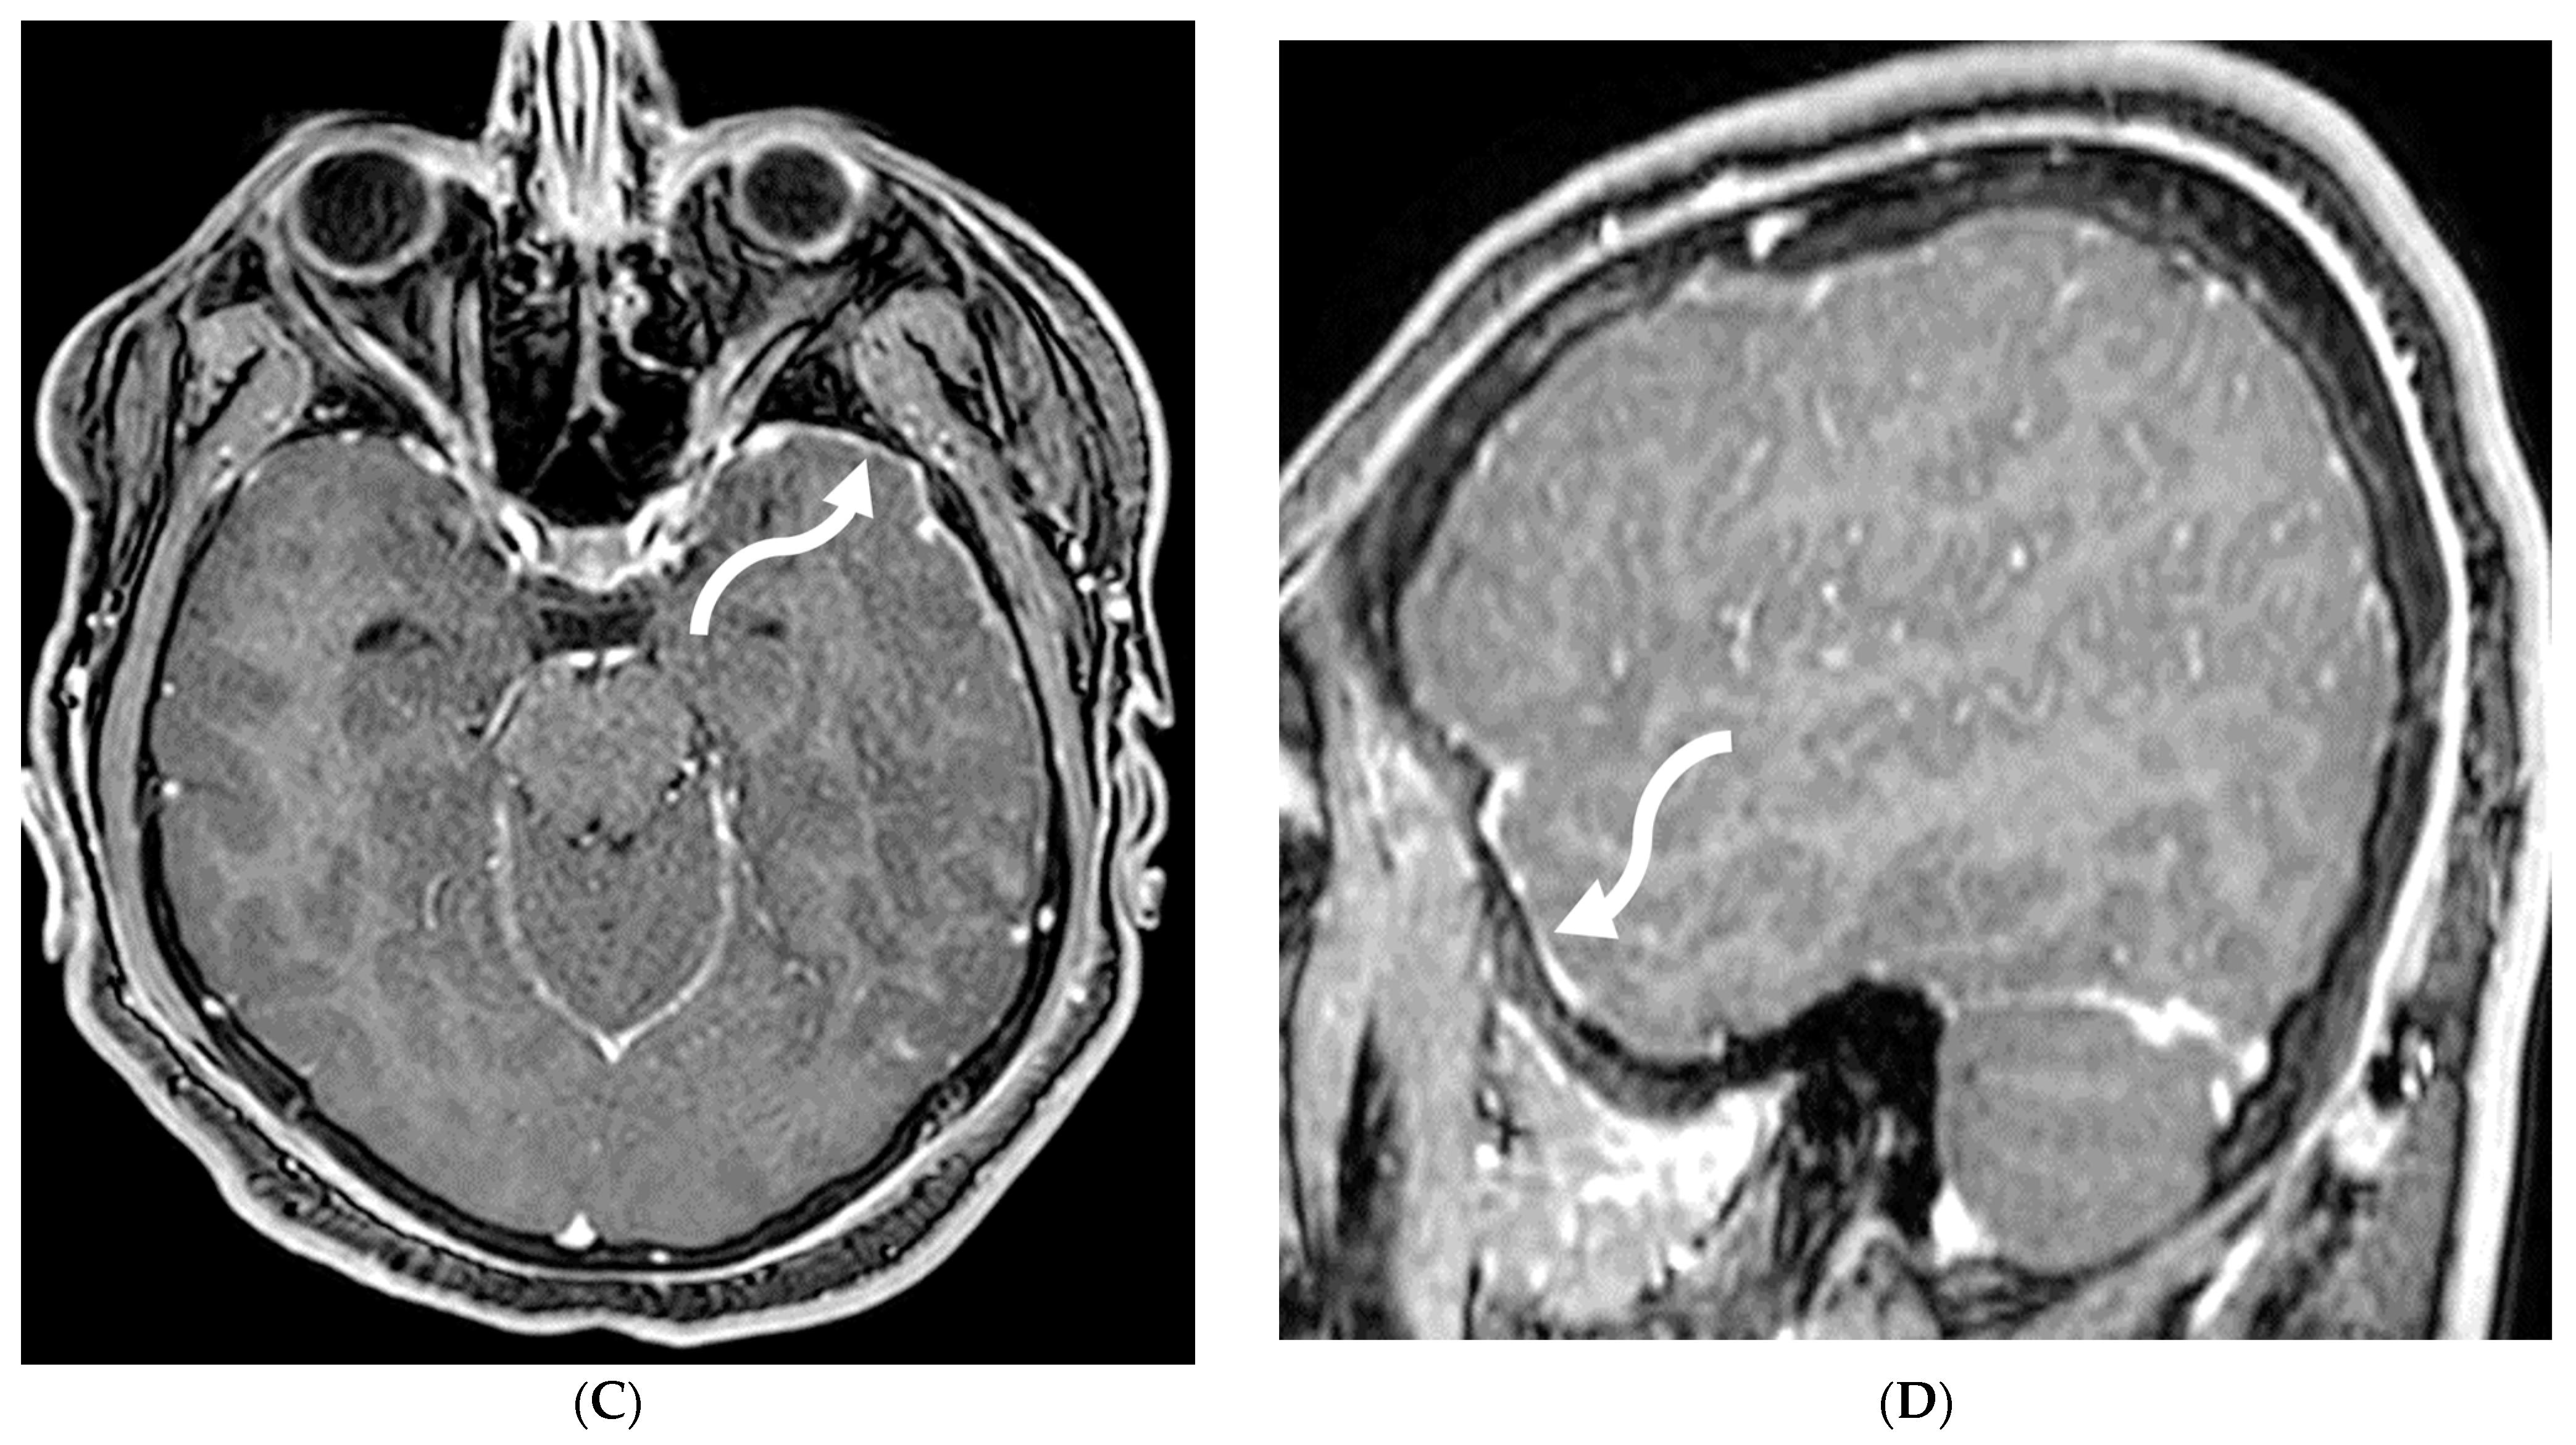

Figure 2.

Post contrast sagittal T1 brain (A), T1 spine (B), axial T1 brain (C) and spine (D): 17-year-old girl with couple of years of fatigue, shuffling gait, back/lower extremity pain. There is moderate ventriculomegaly (white star). Meningeal enhancement is present around the cervical cord (white arrow). Flattened and deformed brainstem & spinal cord diffusely (curved arrows) and enhancing septae (dashed arrows) within the thecal sac are noted likely from chronic meningitis. Basal cistern enhancement (open arrow) and septae (arrow head) in the lateral ventricles likely reflects sequela of chronic inflammation/infection. Pathology: Prototheca Zopfil.